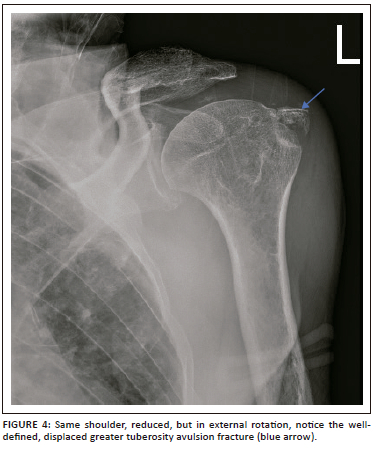

Control plain radiographs are mandatory. Three views must be obtained (anteroposterior, axillary view and lateral view) to confirm the reduction and rule out bony compression fractures of the humeral head (Hill-Sachs lesion), push-off fractures of the glenoid (bony Bankart lesion), bony erosions (glenoid bone loss) or to identify fractures that were initially not visible (Figure 2, Figure 3, Figure 4 and Figure 5). Kahn and Mehta reported a rate of 37.5% of fractures which were visible only on post-reduction radiographs.15